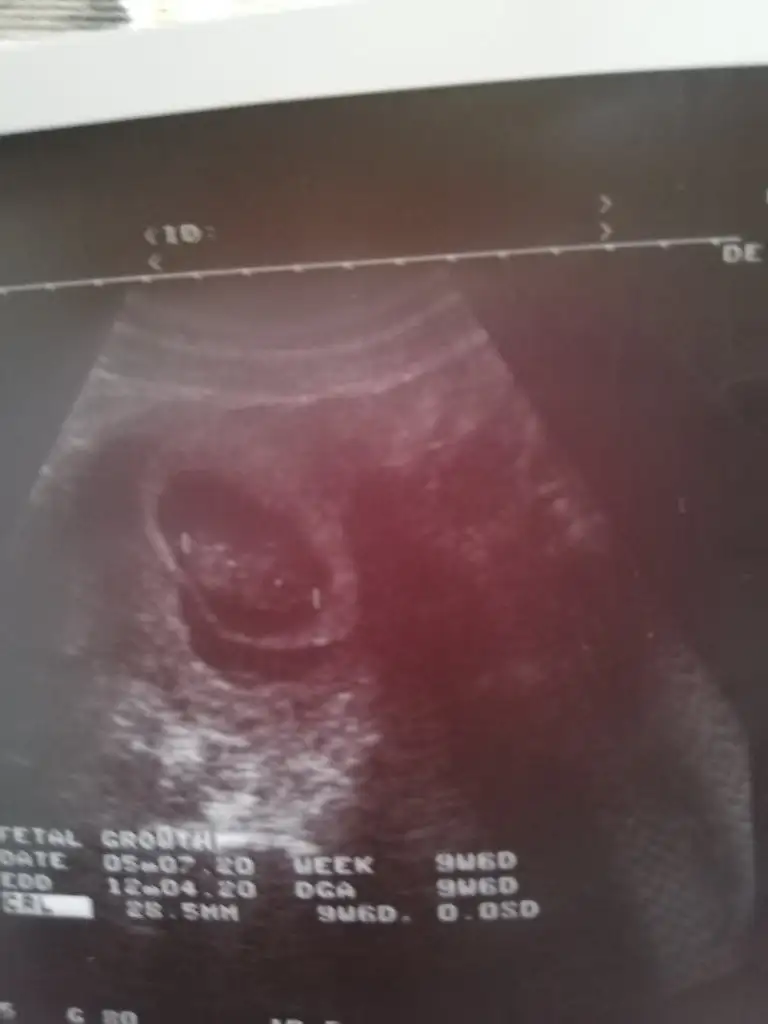

Ay nasil yani kese disinda var saniyordum ben kanamayi doktor oyle demisti icinde kanama nasil oluyo kizKesenin içinde ve dışında varmış seninki benimde kese dışında var foto atmıştım İnş bişey olmaz

Doktor dışı dediyse dışıdır canım sanki ben içinde gibi gördüm benim dediğimi dikkate alma bak benim kanama alanı da böyleAy nasil yani kese disinda var saniyordum ben kanamayi doktor oyle demisti icinde kanama nasil oluyo kiz

Rabbim bagislasin hepimizinkiniDoktor dışı dediyse dışıdır canım sanki ben içinde gibi gördüm benim dediğimi dikkate alma bak benim kanama alanı da böyle